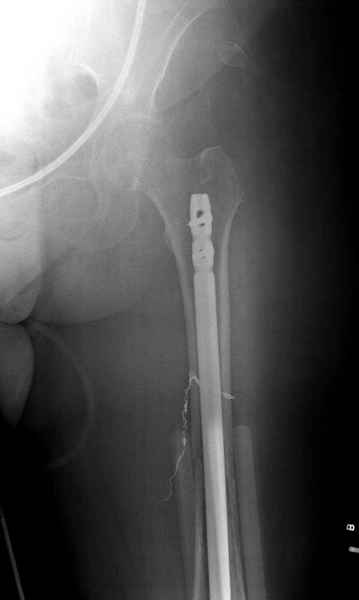

С минимальным рассверливанием и ретроградным методом провели остеосинтез бедра 12 мм гвоздем. (17-20)

Кровопотеря во время операции меньше 100 мл.